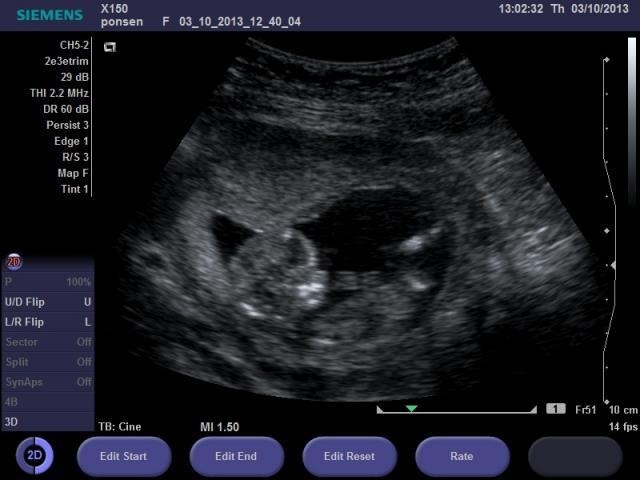

Im going to guess girl from the 3rd picture.

Guessing girl from the 3rd pic too!

I'm not seeing a nub at all.

Lovemy4, you don't? Isn't the nub the white thingy pointing downwords?